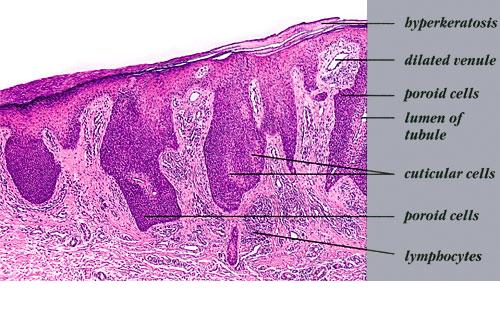

The term poroma refers to a group of rare cutaneous appendage tumors composed of cells (cuticular and poroid cells) similar to those of the acrosyringium. Poromas are traditionally subcategorized histopathologically based on their location in relation to the epidermis into three main variants; namely, hidroacanthoma simplex, eccrine poroma, and dermal duct tumor. Some authors add poroid hidradenoma to this group. There are also reports of “poromas” with differentiation toward the folliculosebaceous-apocrine unit.

Hidroacanthoma simplex shows sharply demarcated aggregations of cuboid to ovoid cells confined to the epidermis. Eccrine poroma reveals aggregations of uniform basaloid cells that radiate from the basal layer of the epidermis into the dermis . Dermal duct tumor consists of several sharply circumscribed, mainly dermal nodules composed of poroid and cuticular cells. Ductal structures are frequently observed. Poroid hidradenoma is characterized by intradermal, solid, and cystic aggregations of poroid cells.